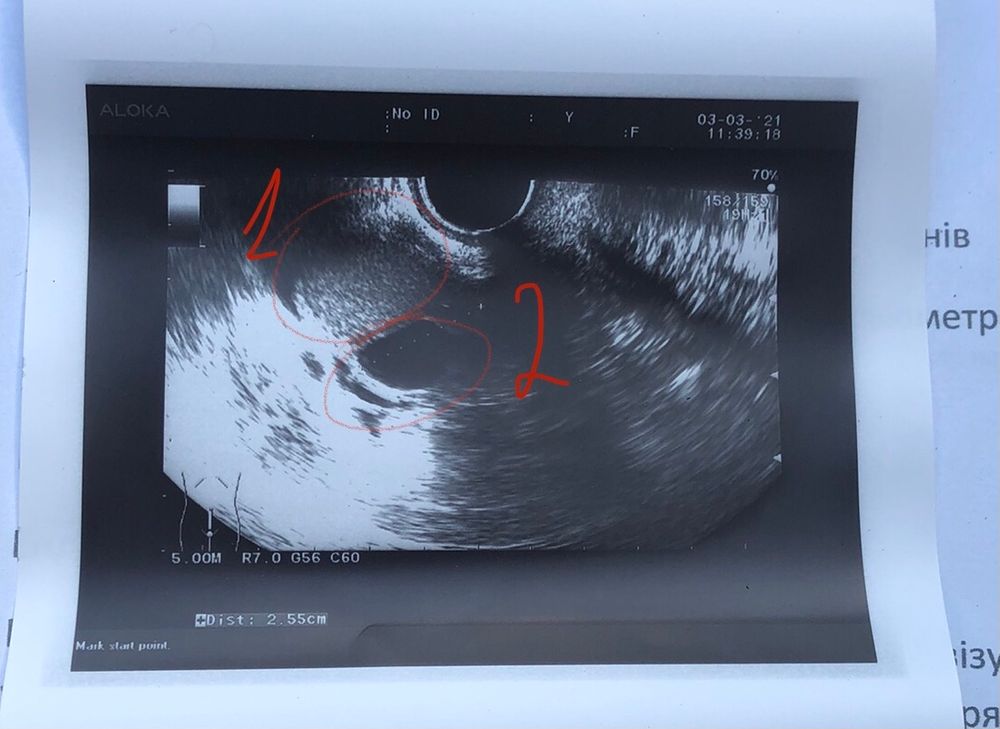

Я снова со своими кистами 🤕

MomS, написано в заключении обе кисты по 2,5 Я стараюсь не думать, но оно конкретно стреляет , прям на секунду зависаю от неожиданных болевых ощущений